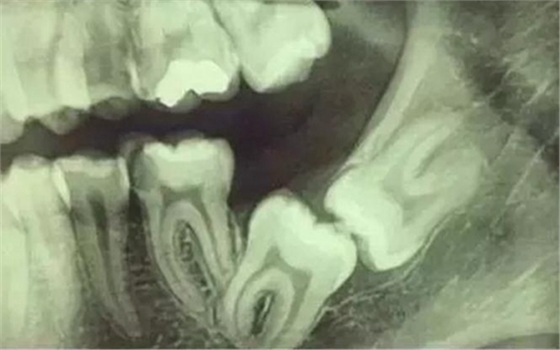

拍片是為了了解智齒周圍情況,也是為了了解智齒結構,牙根結構千變萬化,有可能是融合成一個根,也可能是八爪根。不同牙根不同位置及方向,只有通過拍片來確認。

通過拍片可以了解牙齒本身:生長方向,牙根數目,牙根是否彎曲,膨大等。

與重要解剖結構的位置關系:如上頜磨牙與上頜竇的關系;下頜磨牙與下頜神經管的關系;兒童在混合牙列期恒牙與乳牙胚的關系等??梢詼p少拔牙的風險。